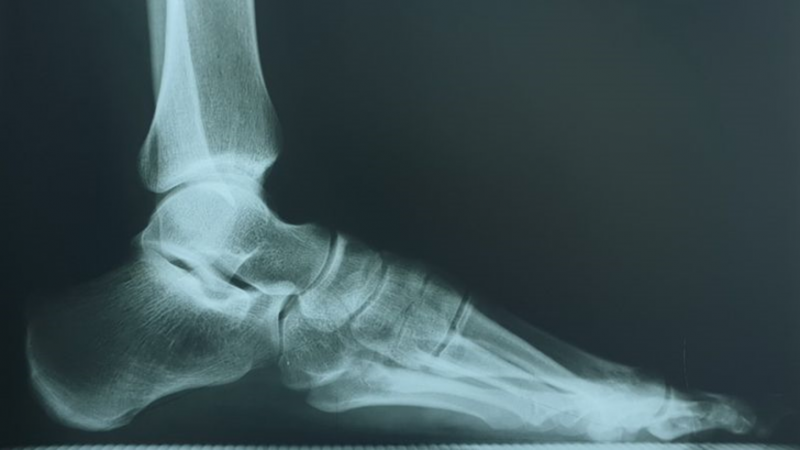

ЯК НАЗИВАЄТЬСЯ ЦЯ КІСТКА?

РОЗПІЗНАЙТЕ КІСТКУ. ПЕРЕЛОМ ЯКОЇ ЇЇ ЧАСТИНИ ВИ БАЧИТЕ НА РЕНТГЕНОГРАМІ?

ДЕ ВИ БАЧИТЕ СУГЛОБ, ЯКИЙ ЗАБЕЗПЕЧУЄ РУХИ СТОПИ.

СУГЛОБ УТВОРЕНИЙ СУГЛОБОВИМИ ПОВЕРХНЯМИ ЛАТЕРАЛЬНОЇ І МЕДІАЛЬНОЇ КІСТОЧКИ ТА ТІЛОМ ТАРАННОЇ КІСТКИ. РУХИ НАВКОЛО ФРОНТАЛЬНОЇ ОСІ. ЧАСТО - РОЗТЯЖІННЯ, ВИВИХИ, РОЗРИВИ, ПЕРЕЛОМИ. РОЗПІЗНАЙТЕ СУГЛОБ.

ГОМІЛКОВО-СТОПНИЙ С.

СУБКОСТАЛЬНИЙ КУТ